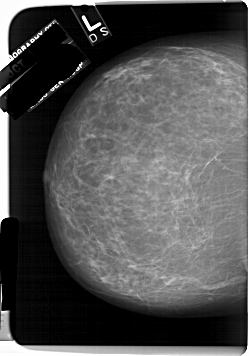

A_1232_1.LEFT_MLO

A_1232_1.LEFT_CC

LEFT_CC LINES 6751 PIXELS_PER_LINE 4726 BITS_PER_PIXEL 12 RESOLUTION 43.5 NON_OVERLAY

LEFT_MLO LINES 6661 PIXELS_PER_LINE 4966 BITS_PER_PIXEL 12 RESOLUTION 43.5 NON_OVERLAY